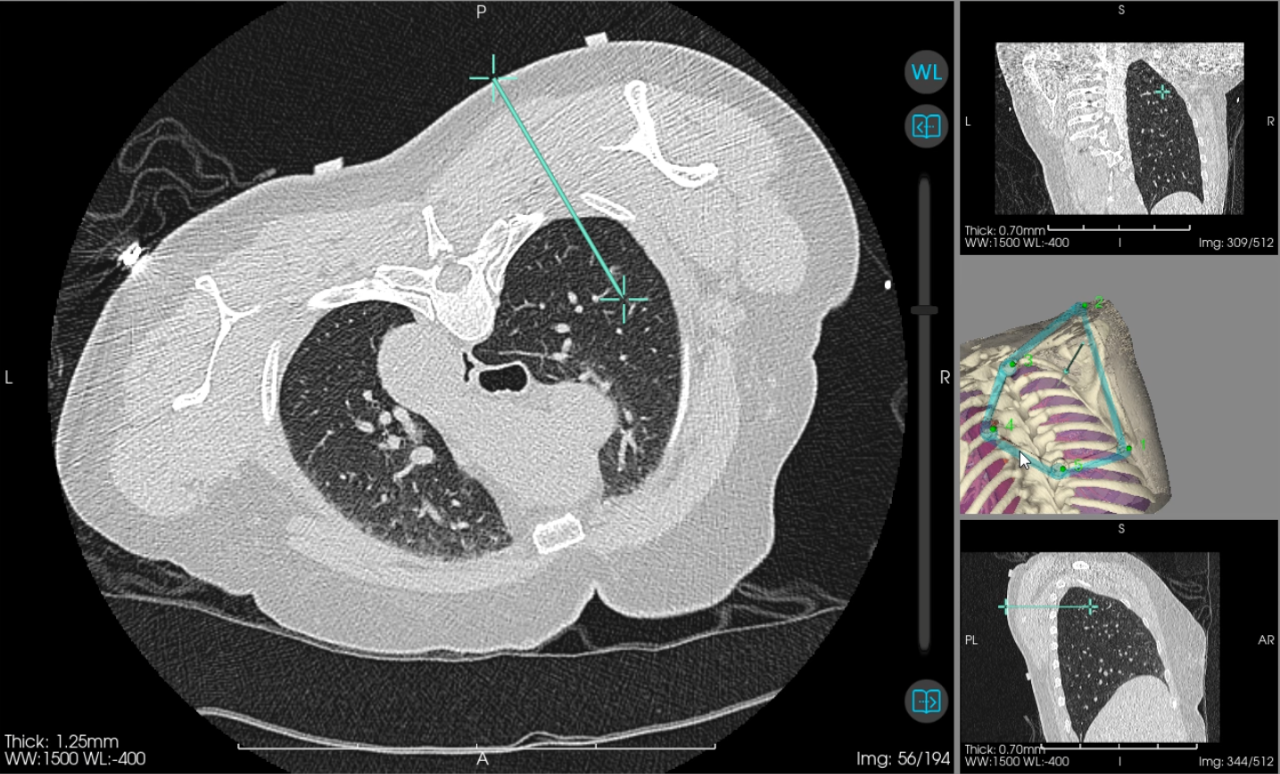

当天,心胸外科主任阳诺带领消融团队开展手术。他介绍,在术前,穿刺手术机器人系统基于患者 CT 影像,能自动构建详细的肺部 3D 立体模型, 清晰呈现结节与周围血管、气管等重要组织的位置关系。

「它就像一位『智能导航员」,精准规划穿刺路径、角度与深度,有效避开血管、气管等重要组织结构,将误差控制在毫米级。」阳诺说。

术中,机器人就像有了「智慧眼睛」和「稳定双手」,整个过程机械臂平稳导航,无需调针,实现对靶病灶的「一针到位」,减少了 CT 扫描次数和患者的辐射暴露。机器人的应用避免了人为因素可能带来的穿刺偏差,从而大大减少了对周围正常组织的损伤,显著降低了气胸、出血等并发症的发生率,也显著缩短了手术时间。

快速精准定位一直是肺结节介入诊疗的核心环节。 目前 CT 引导下经皮肺肿瘤消融治疗、经皮肺结节穿刺定位术、经皮肺肿瘤穿刺活检术等均依赖于高超精准的穿刺技术。传统穿刺方式高度依赖操作者的手感与临床经验,精准的穿刺技术学习周期长,对于刚接触肺肿瘤穿刺技术的医生,实际操作穿刺路径可偏离靶病灶几度甚至到十几度,从而导致多次 CT 扫描并反复调针,耗时长,还会增加出血、气胸等并发症发生率及辐射暴露。而机器人穿刺导航系统可复刻规划好的穿刺路径,彻底改变了传统操作模式。